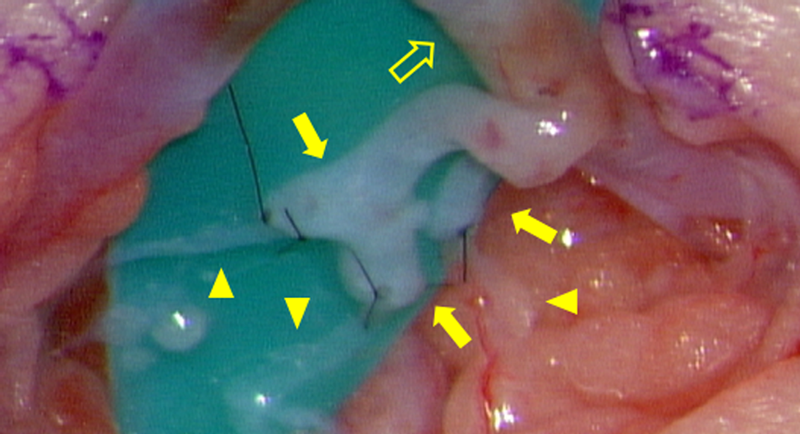

Pediatric Cardiology and Cardiac Surgery 34(3): 135-142 (2018)

Fig. 4 The concept of etiology of central lymph diseases, and surgical treatments

Single circle: Pooled lymph, Interrupted circle: Leaking, Double circle: Lymph into or out from the central system.

LGはリンパ管を通じて粘性の高い造影剤が胸腔内に流出する.直接的な塞栓または漏出部位で周囲組織に炎症反応を惹起することで,選択的な癒着術を起こすと考えられている.合併症としてリンパ浮腫の発症に注意が必要とされる.われわれはリンパ管造影に先行させてICGを併用する方法(ICG-LG)を頻用する20).LG後の下肢浮腫を早期診断するにあたり,追加の造影剤注入を必要とせず小児に適した方法と考えられる.またLGは右左シャントがある場合に脳血流へ造影剤が混入し脳梗塞を起こすことがあり21),当院ではシャントを有する患児は対象外としている.肺塞栓を起こす可能性は否定できないが,自験例における術後呼吸状態の悪化は見られなかった.静脈流入後はLGの追加注入をしないように注意している.

LVAはわれわれが好んで用いる,リンパ流再建の主要な方法である.主に成人の二次性リンパ浮腫に対して,本邦を中心に発展してきた22).小切開,浅層操作で完了し低侵襲であり,成人では局所麻酔で施行できる23).リンパ液は正常解剖でも静脈へ流れ込むため,比較的自然な再建法である24)Fig. 5).機序として下肢から中枢リンパ路へ回収される経路を静脈へ逃すほか,体表へ逆流したリンパ液を静脈系へ回収すること,静脈系の止血因子を有した血液が少量リンパ路へ混ざることで漏出部に癒着を起こすこと,などが考えられる25)

Fig. 5 Lymphatic venous anastomosis, Intraoperative findings (Case #1)

Arrow head: Lymph vessel, Arrow: Branches of the Vein, Empty arrow: Main trunk of the Vein. Vein branches were enlarged with lymph fluid, result in clear expansion. In this case, three lymph vessels were anastomosed to three branches of the vein. Outer diameters were 1.0 mm for Main trunk of the vein, 0.6 mm, 0.35 mm for branch of the vein, and 0.2–0.3 mm for Lymphatic vessels.